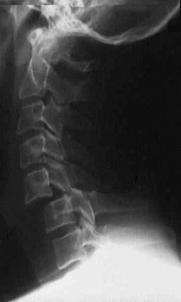

TRAUMA CERVICALA

Incidenta laterala Incidenta

laterala Incidenta

antero-posterioara

Aspect normal Imagine

incompleta Aspect

normal

Incidenta occipitomentala (odontoida)

Aspect normal Incidenta

oblica

Aspect normal

Incidenta oblica Incidenta laterala Incidenta antero-posterioara

Aspect normal Aspect normal Aspect normal